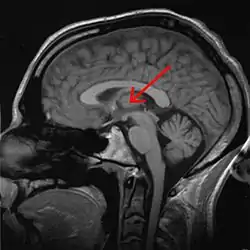

![]() Thalamus marked (MRI cross-section) | |